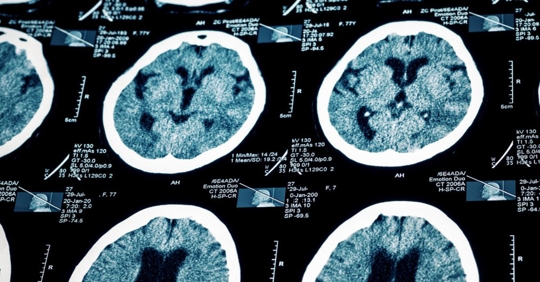

Mild TBIs often arise from everyday events — slips and falls, car crashes, sports accidents, and workplace impacts. Even when a blow to the head seems minor, or there is no direct trauma at all, the brain can move suddenly inside the skull, creating bruising or damage to delicate neural pathways. These internal injuries are not always visible on standard imaging, which is why they are frequently misunderstood or overlooked.

Mild TBIs can be difficult to diagnose. Symptoms often overlap with conditions such as PTSD, depression, migraines, or chronic fatigue, leading some patients to be misdiagnosed or dismissed altogether. Advanced imaging tools, now more frequently used in Maine’s medical community, can help identify subtle brain changes; however, clinical evaluation remains essential.